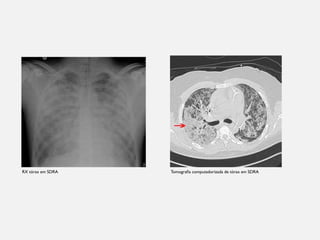

RX tórax em SDRA Tomografia computadorizada de tórax em SDRA

TRATAMENTO HIPOXEMIA: ESPECÍFICO PARASDRA • Efeito shunt (principal exemplo) • Critérios diagnósticos • SDRA de causa pulmonar ou extrapulmonar • Avaliar índice de oxigenação através da relação PaO2/FiO2 • Classificação da SDRA em leve, moderado ou grave PILARES DO TRATAMENTO

RX tórax emSDRA Tomografia computadorizada de tórax em SDRA